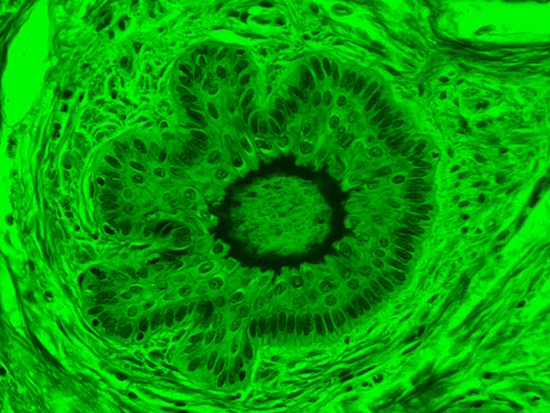

Figure 4: Brightfield Image of Dermal Tissue filtered with Red

When comparing Figure 3 with Figure 4, there is once again a significant visual difference. The most obvious feature is the change in color from green to red due to a different hardcoated filter being positioned in the optical path. The less obvious difference is the varying contrast levels caused by the filters at specific regions of the dermal tissue. For example, Figure 3 exhibits a distinct ring at the central region of the cell with additional matter within. In Figure 4, the ring is extremely faint and the internal matter is not visible. With that said, the cell and surrounding dense materials are more evident in Figure 3, whereas the muscle fibers and collagen are more pronounced in Figure 4.